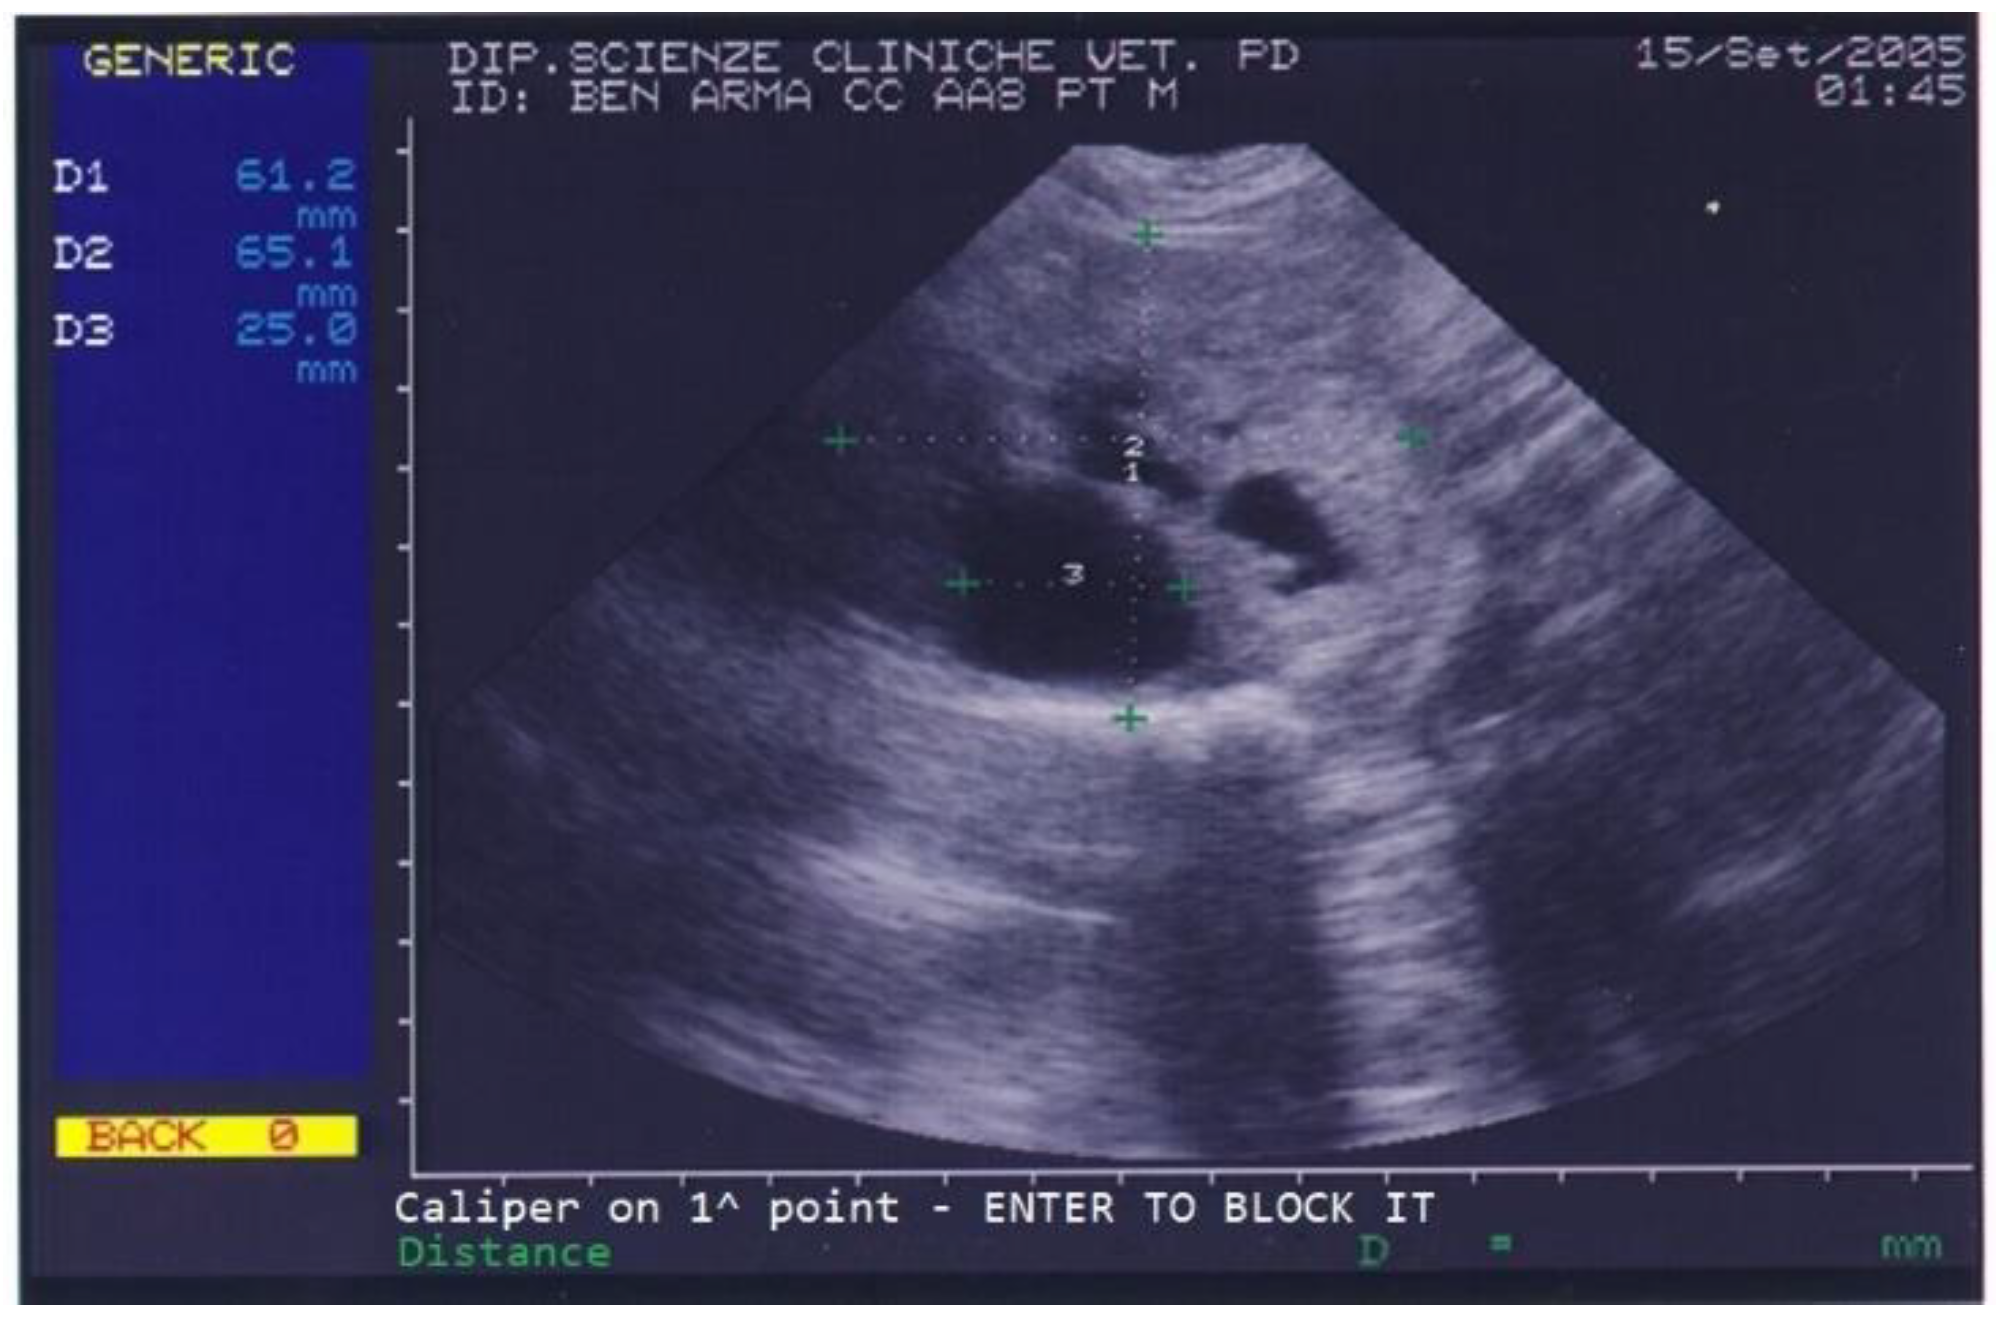

Benign prostatic hyperplasia (BPH) and purulent otitis were diagnosed, and an antibiotic treatment was prescribed. Two weeks after treatment, the dog’s conductor reported that the dog’s skin and ear condition as well as his ability to work had improved but appetite was still poor and defecation was still difficult. The prostate was not painful on palpation. A blood sample was collected for a complete blood count (CBC) and serum biochemistry evaluation. CBC revealed mild eosinophilia while biochemical parameters were normal except for high total proteins (88 g/L) and high albumin (36 g/L). Urinalysis revealed the presence of erythrocytes (250 cell/L), leucocytes (25 cell/L) and proteins (25 mg/dL) in urine. On prostatic ultrasound, the prostate was regarded as similar to the previous exam (Figure 2).

Figure 2.

Abdominal ultrasonography of a German shepherd dog before deslorelin implant. The scan shows the ultrasonographic appearance of the prostate and the presence of different-sized cysts. The prostate’s perpendicular diameters are measured as D1 = 61.2 mm and D2 = 65.1 mm. The largest prostatic cysts’ diameter is measured as D3 = 25 mm.